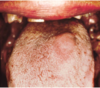

Erythematous

Candidiasis

what are its

Clinical finding?

Subtypes?

● Clinical Findings:

- Red macules or patches

- Can be due to multiple things

● Subtypes:

‐ Atrophic Candidiasis (acute‐feels like mouth has been scalded)

‐ Median Rhomboid Glossitis (asymptomatic)

‐ Denture Stomatitis (asymptomatic)

■ HAS THE SHAPE OF THE DENTURE

‐ Chronic multifocal (asymptomatic)

■ THIS HAS BEEN THERE FOR A LONG TIME